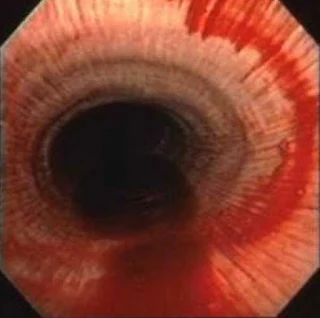

The disease is not always clinically present, but after environmental challenge, horses show moderate to severe expiratory dyspnoea, next to nasal discharge and cough. The onset of the disease is caused by inhalation of environmental allergens, especially hay dust, that cause severe bronchospasm and in addition hypersecretion. The mucosa becomes swollen while accumulated mucous secretions further contribute to airway narrowing.

The visible morphological changes are primarily located in the small airways and spread reactively to the alveoli and major air passages. Lesions may be focally, but functional changes may manifest themselves well throughout the bronchial tree. Bronchial lumina may contain a variable amount of exudate and may be plugged with debris. The epithelium is infiltrated with inflammatory cells, mainly neutrophil granulocytes. Furthermore, epithelial desquamation, necrosis, hyperplasia, and non-purulent peribronchial infiltrates may be seen. Fibrosing peribronchitis spreading in neighboring alveolar septa was reported in severely diseased animals The extent of these changes in the bronchioles is related to a decrease in lung function, but changes may be distinctly focal in nature.